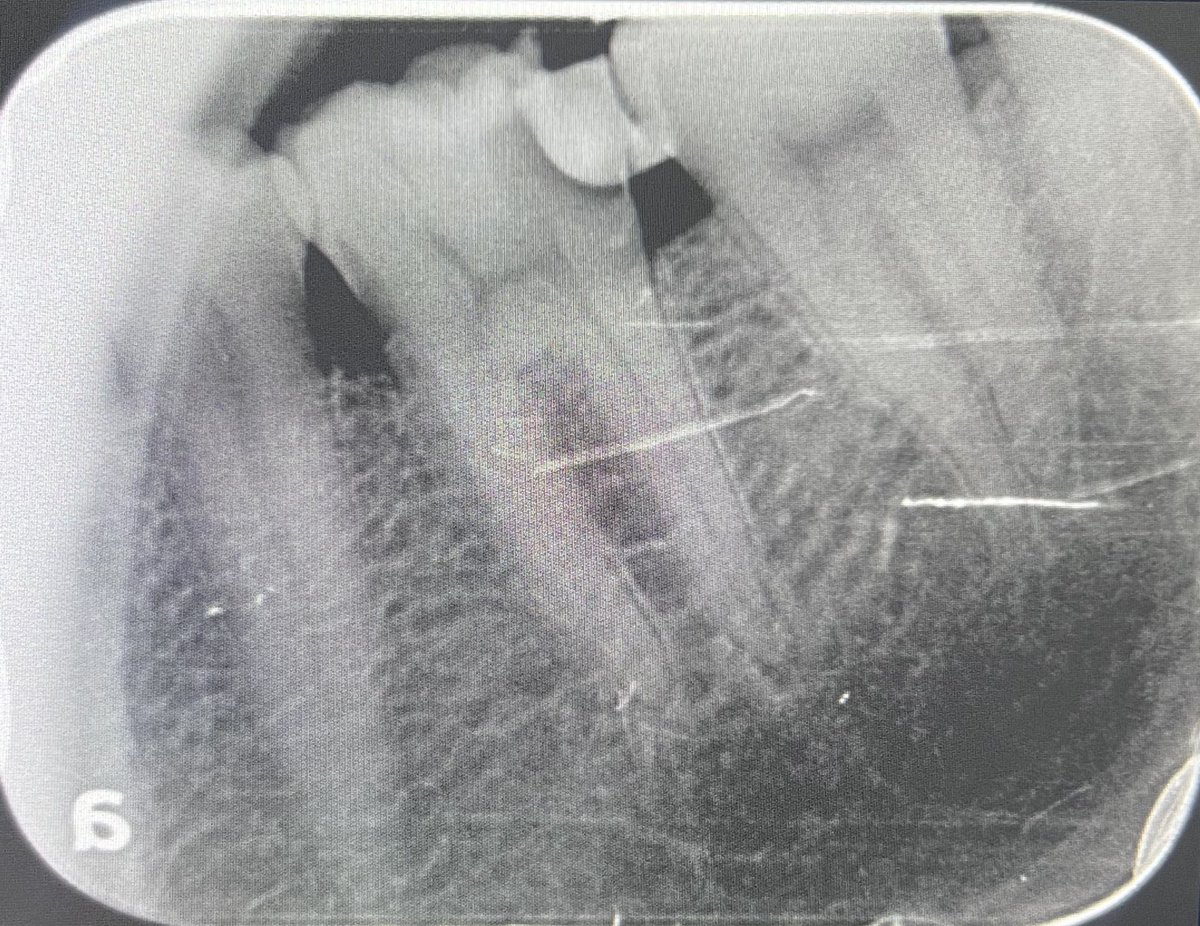

Today’s case:

Rct of #11 Dx : PI/AAA

• 1st visit: Open access, irrigation, abscess drainage, and dressing the canal with Ca(OH)₂.

• 2nd visit (after 30 days): Reopening the tooth, irrigation performed; the canal was completely dry and ready for obturation.

Patient is fine😁